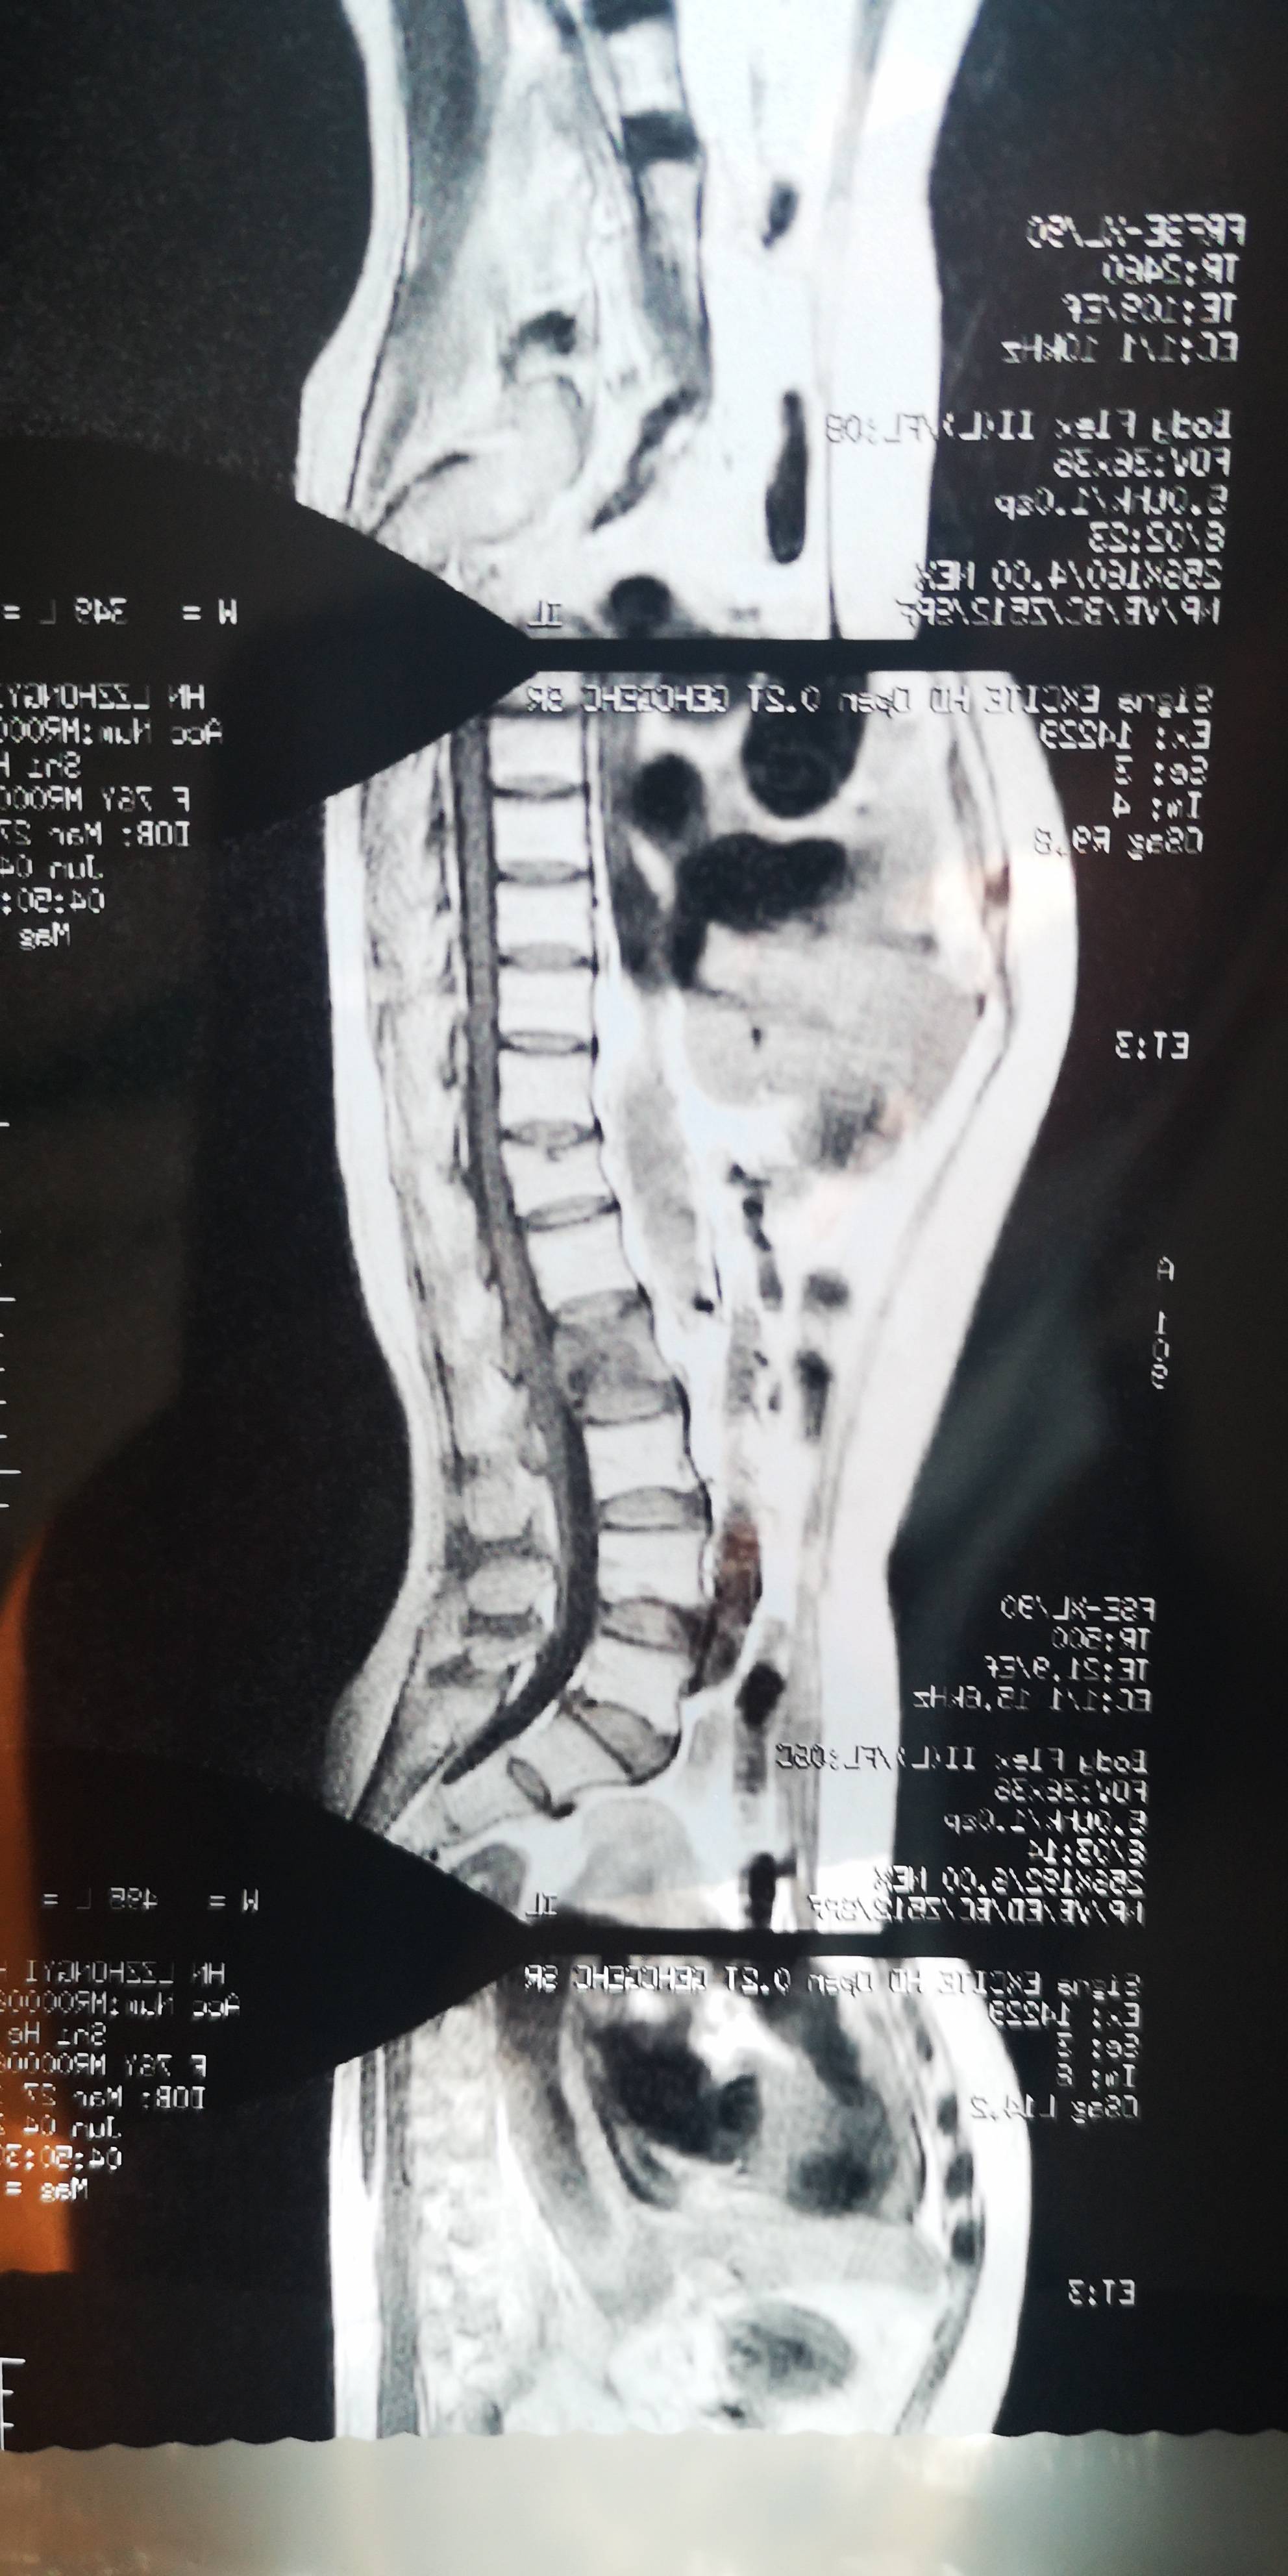

2021年6月6日腰部磁共振显示,腰椎二骨转移严重(由于3月份的头颈胸腹未提示腰椎骨转移,所以我猜是放疗期间发生转移的)。随双氯芬酸钠栓24小时一粒,病人方得安宁。